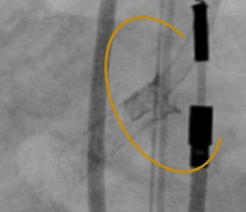

RCA Ostial Stenosis

Prior to stent deployment

Stent protruding into aorta

Post-dilatation with FLASH

TRUE 360° result